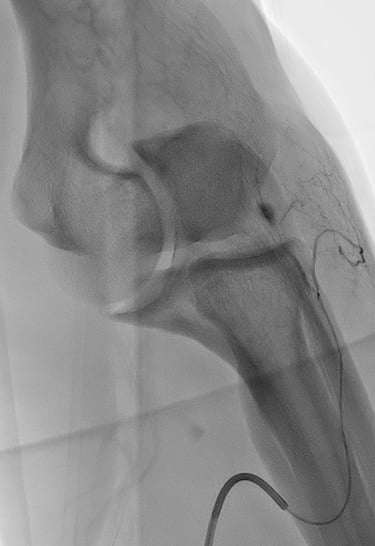

A l’aide d’un abord vasculaire artériel au niveau du poignet ou de la jambe , un cathéter est envoyé dans les vaisseaux de la zone concernée (épaule ou coude le plus souvent).

Une artériographie par injection de produit de contraste iodé est réalisée. Elle permet la cartographie des artères pour dépister les zones d'hypervascularisation, qui sont le témoin de l'inflammation locale. Ces zones sont le plus souvent concordantes avec les douleurs rapportées par le patient.